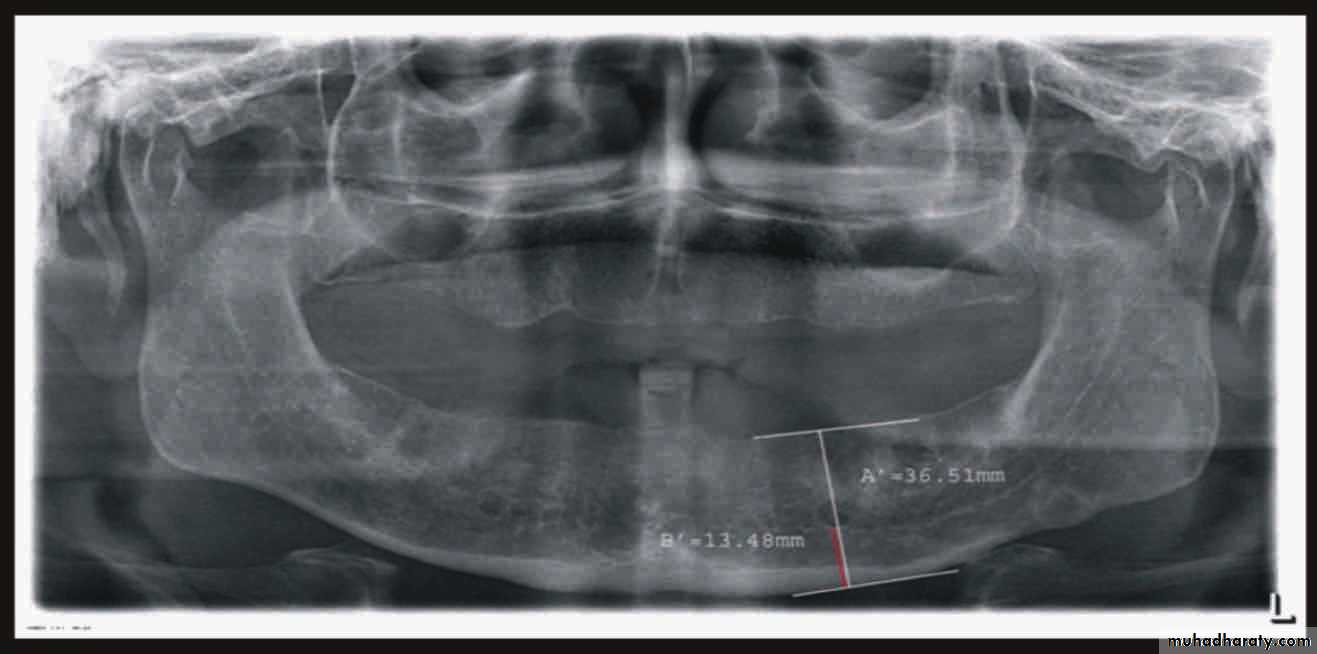

Radiographic examination:• Cyst

• Tumor• Retained root

• Periodontal condtion of remaining teeth

• Bone fracture

• Extend of bone resorbtion

• Locate cannal

• pt. education